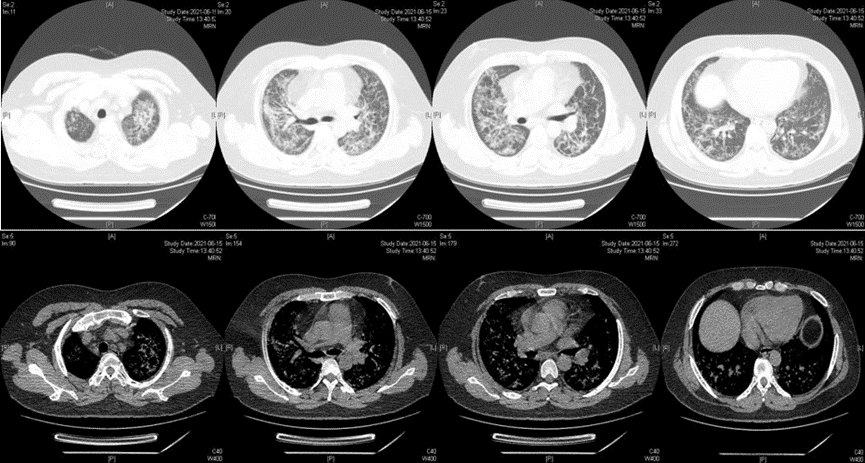

• 1天前肺CT提示双肺间质改变(图1),较2020年12月21日明显进展,排查新冠肺炎后,于2021年6月16日收入院,给予经鼻高流量吸氧,甲强龙80 mg q12h,头孢哌酮舒巴坦+盐酸莫西沙星+更昔洛韦抗感染,患者氧合不能维持,于6月17日转入RICU。

图片

图1  患者胸部CT